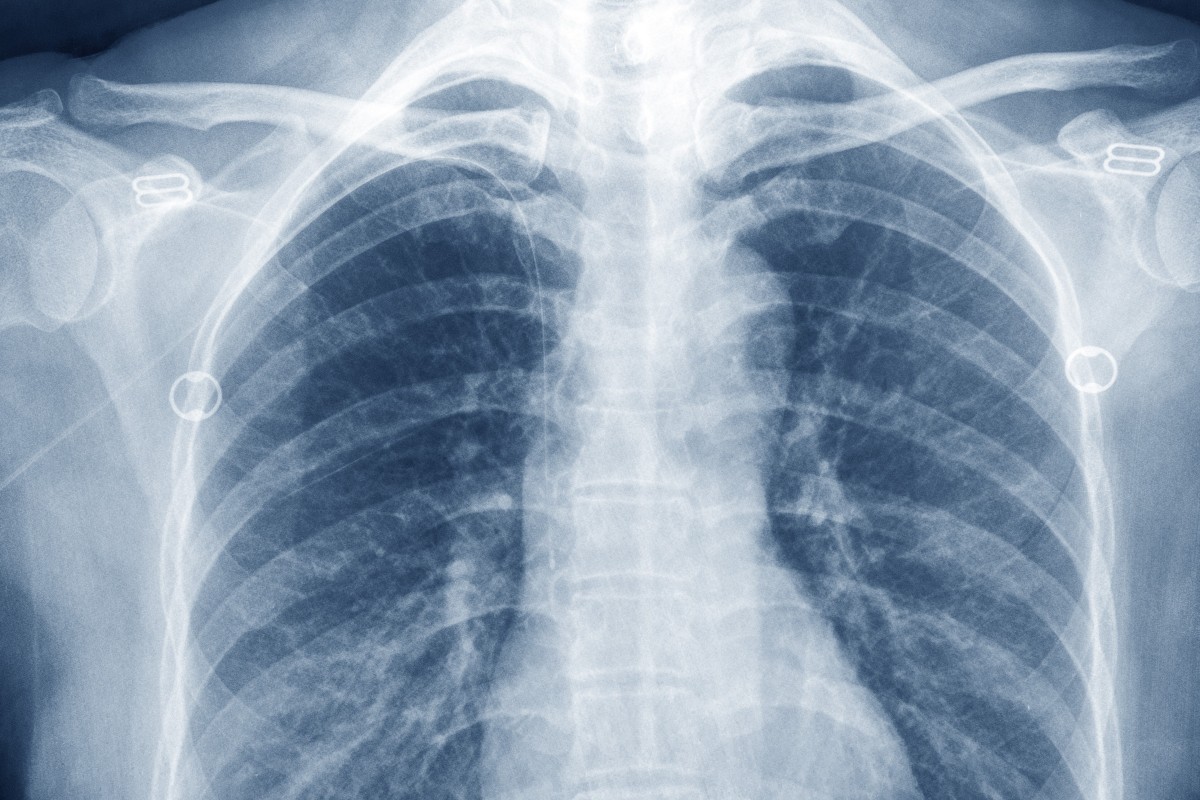

Normal radiographic measurements of the shoulder are important in evaluation of the osseous relationships in plain film radiography. Overview an x ray is a quick painless test that produces images of the structures inside your body particularly your bones. Am j dis child. The dimension to be measured is the thickness through which the x ray beam will pass. Mas x ray quantity increases in direct proportion to increases in. X rays are a vital imaging tool used around the globe.

Thus analysis of x ray images of the body is a valuable medical diagnostic tool. Dense materials such as bone and metal show up as white on x rays. Mass and weight measurement with x ray technology is a reality providing an additional layer of process control and due diligence to ensure a high quality defect free product. X ray electromagnetic radiation of extremely short wavelength and high frequency with wavelengths ranging from about 10 8 to 10 12 metre. X ray beams pass through your body and they are absorbed in different amounts depending on the density of the material they pass through.